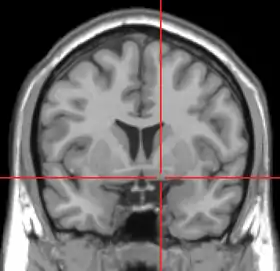

![]() يظهر التصوير بالرنين المغناطيسي المستوى الإكليلي للرأس مع علامات تبين موقع المادَّة اللَّامُسَمَّاة، المنطقة التي توجد فيها النواة القاعدية. | |